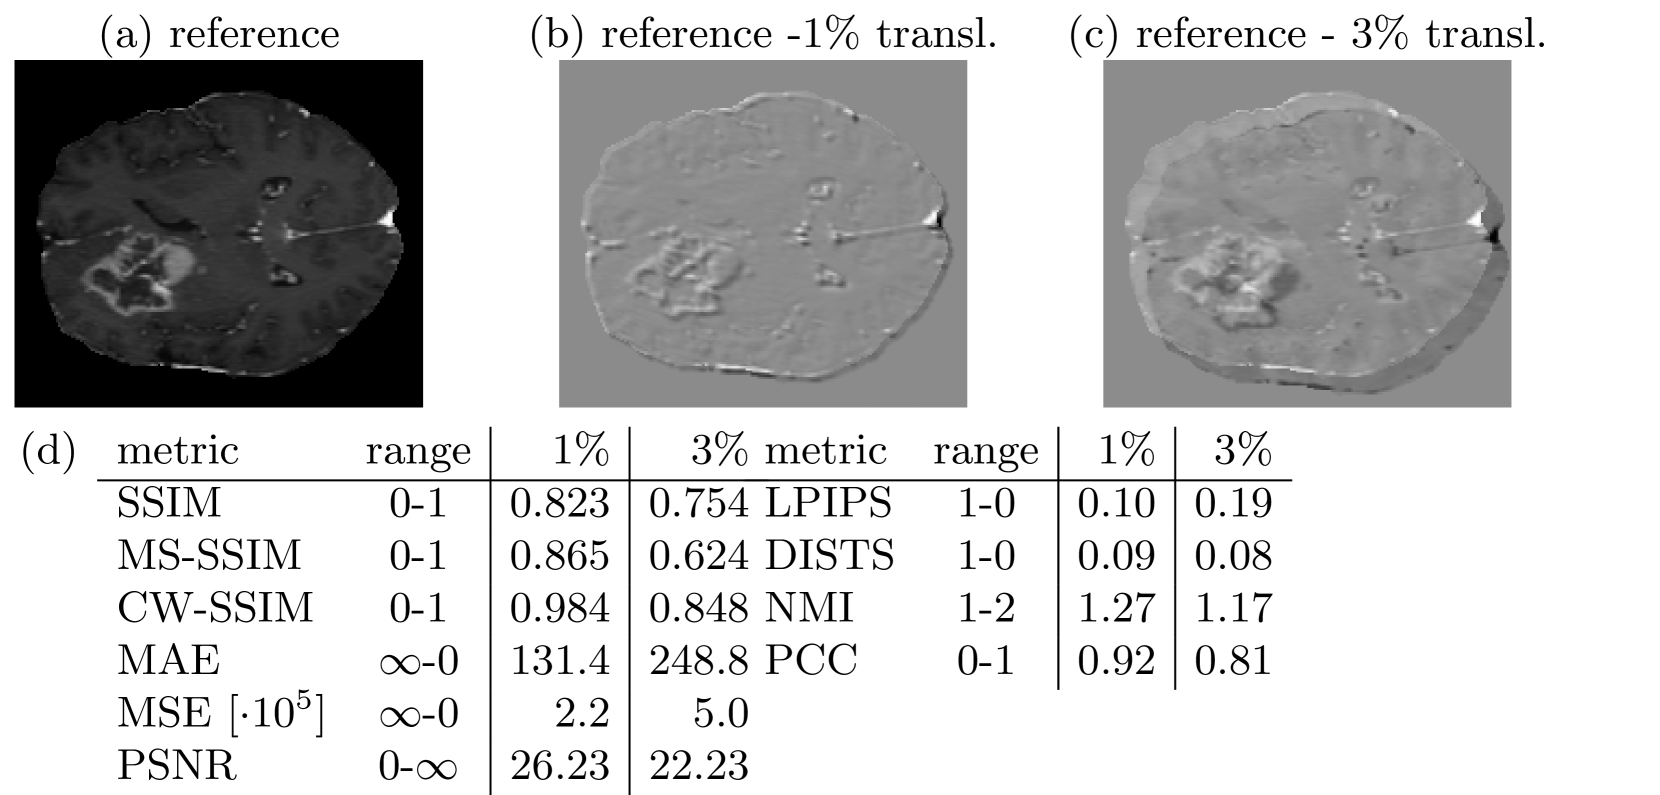

3.2 Pitfall 2: Similarity of Misaligned Images

In image-to-image translation, the source domain input image and the target domain image are often misaligned, because both images were acquired at different timepoints or even with different devices. Therefore, an image synthesized from a misaligned input image is also often misaligned. However, in most cases, medical images are perceived as similar and interpreted in the same way, regardless of small spatial misalignments. Fig. 2 shows that small translations, that are hardly visible, significantly affect most metric scores. Only CW-SSIM and DISTS do not show large changes as they were designed and reported to be less sensitive to misaligments.

Figure 2: Small misalignments have strong influence to all reference metrics. Only DISTS and CW-SSIM are less sensitive to small geometric transformations.